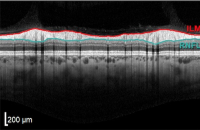

Gesunde Netzhaut

Gleichmäßige, glatte Schichten. Dickere RNFL rechts konsistent mit dem zur Nase hin gelegenen Papillomakulären Bündel.